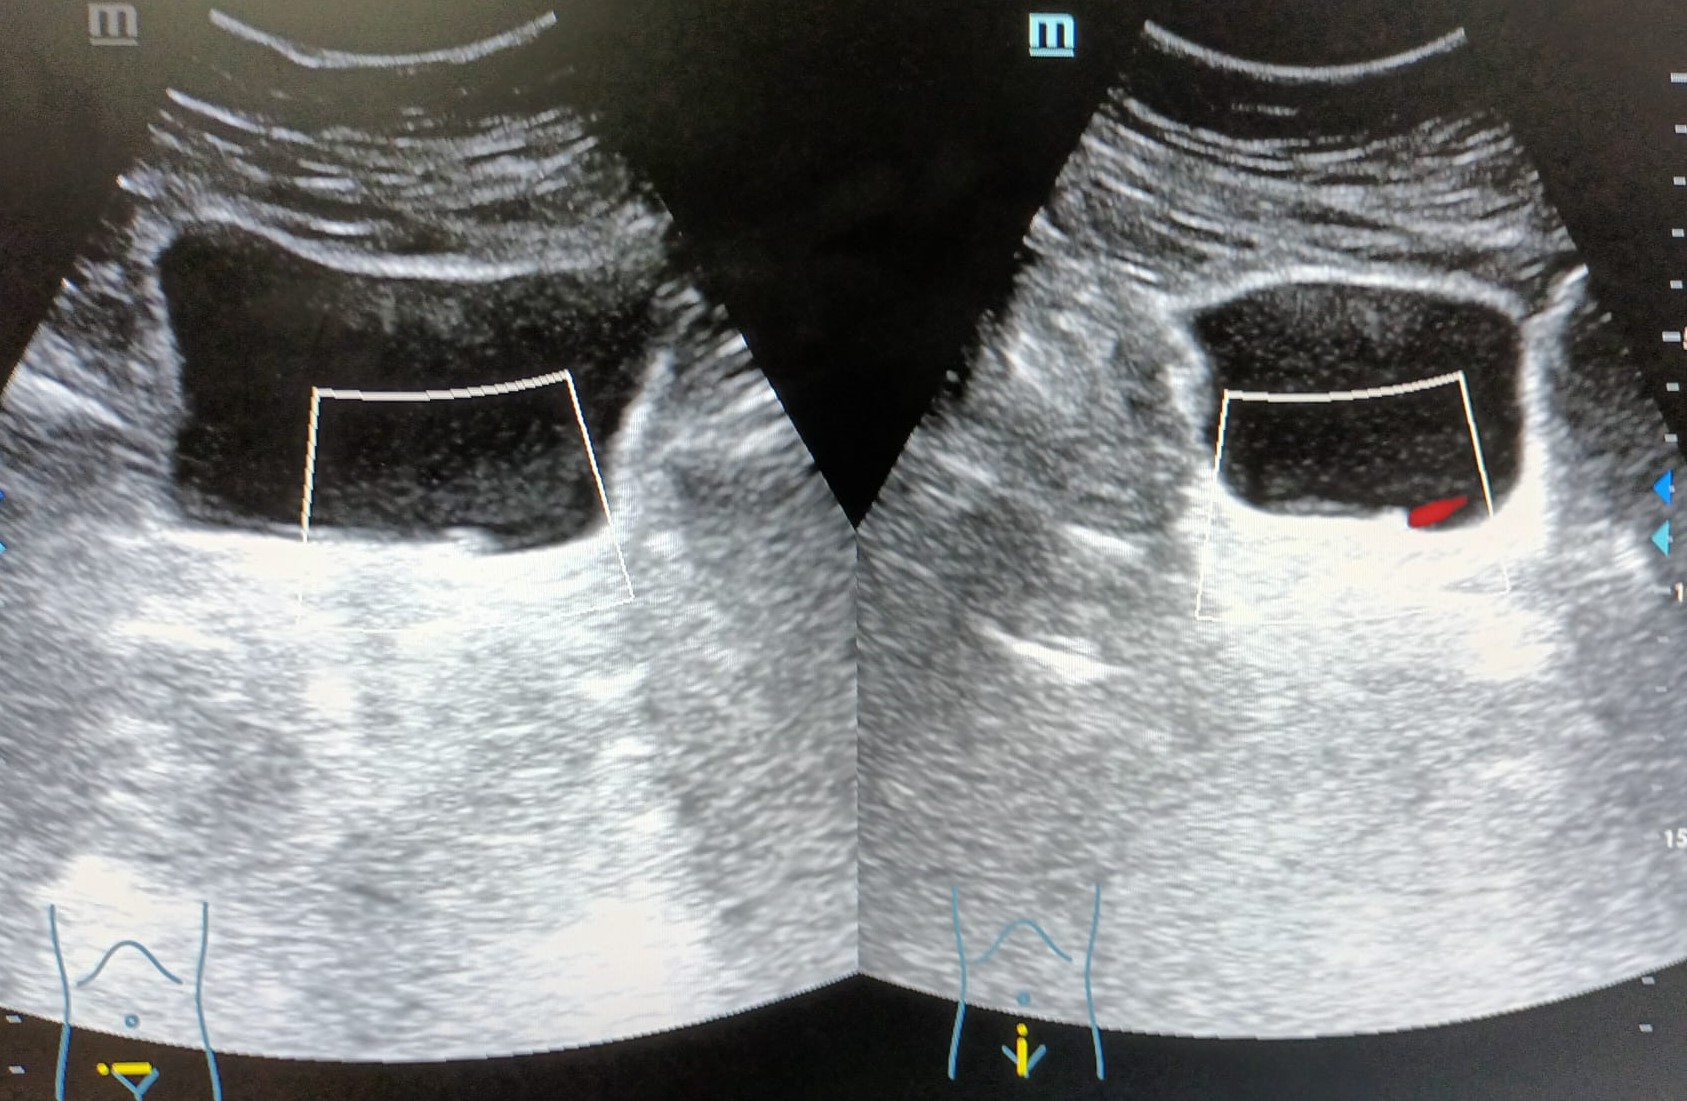

Vejiga: lesión hiperecogénica, de bordes bien definidos, adherida a pared, en zona del trígono vesical, colindante con uréter izquierdo, que no capta Doppler, de aproximadamente 4,2 x 6,7 mm.

Por los antecedentes de microhematuria intermitente y tabaquismo se debe descartar fundamentalmente una neoformación vesical.

Ante el hallazgo ecográfico de una lesión vesical es necesario hacer diagnóstico diferencial entre distintas entidades como pueden ser neoplasias vesicales, ureterocele, litiasis, coágulos, etc.

El Servicio de Urología confirma que se trata de una neoplasia vesical.